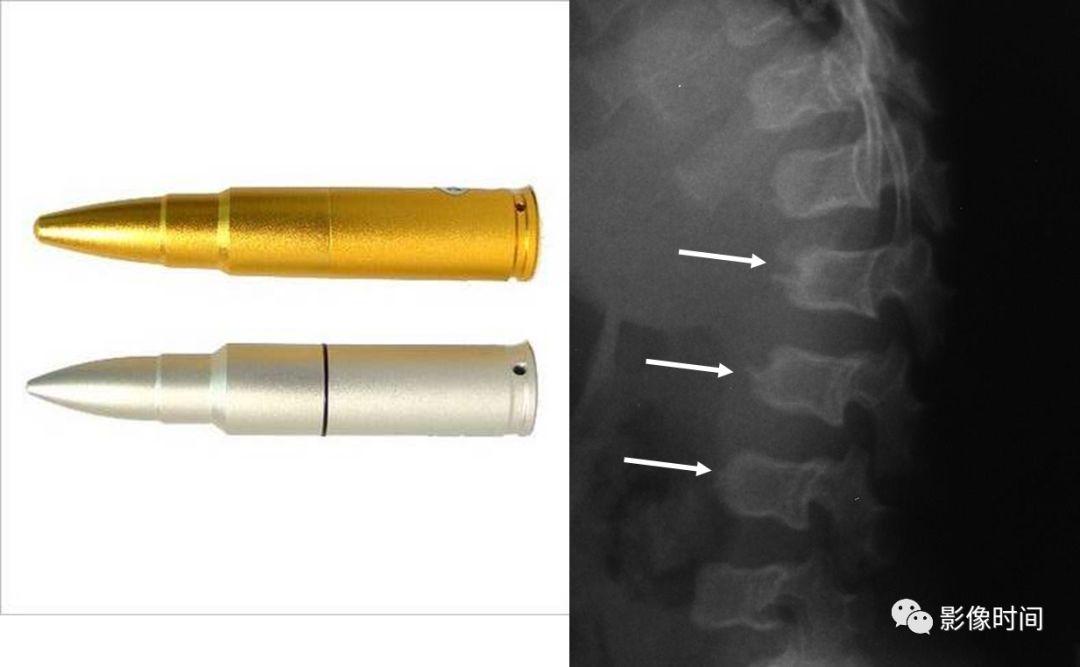

27子弹形椎

子弹形椎(Bullet-shaped vertebra)

子弹形椎指的是椎体的一种形态,即椎体前部呈楔形变尖,类似子弹样。

此名称一般用于描述软骨发育不全的椎体形态改变,但也可以见于黏多糖病和先天性甲状腺功能减退。

(引用自:https://radiopaedia.org/articles/bullet-shaped-vertebra-3)

典型病例

病例 1,5 月男孩,软骨发育不全。脊柱侧位片课件胸腰段后凸,部分椎体呈子弹形(黑箭)。

病例 2,2 岁男孩,软骨发育不全。腰椎侧位片可见椎体呈子弹形(黑箭),另外还可以见到椎体后缘扇贝样凹陷,正位片课件典型的腰椎弓根间距逐渐缩小(红线)。